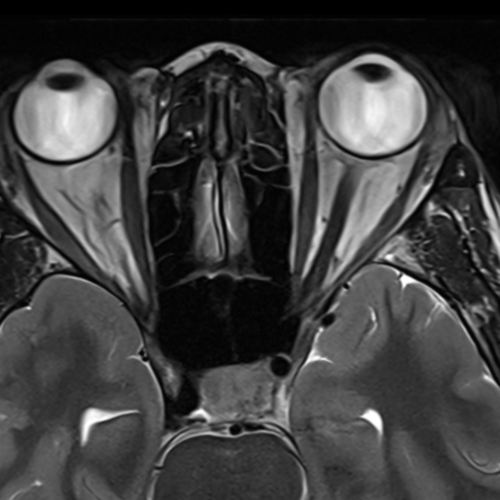

Cet examen est réalisé pour analyser les différentes structures anatomiques des orbites : globes oculaires, nerf oculo-moteurs, nerf optique. Une IRM cérébrale est généralement réalisée dans le même temps.

Cette examen permets de diagnostiquer:

1. Pathologies tumorales

Méningiome du nerf optique

Gliome du nerf optique

Hémangiome caverneux orbitaire

Lymphome orbitaire

Métastases orbitaires

2. Pathologies inflammatoires

Orbitopathie dysthyroïdienne (liée à la Maladie de Basedow) : épaississement des muscles oculomoteurs.

Pseudotumeur inflammatoire orbitaire : inflammation non spécifique des tissus orbitaires.

Cellulite orbitaire

3. Pathologies vasculaires

Fistule carotido-caverneuse

Malformation artérioveineuse orbitaire.

4. Pathologies du nerf optique

Névrite optique (souvent associée à la Sclérose en plaques).

Atrophie du nerf optique.

Compression du nerf optique.